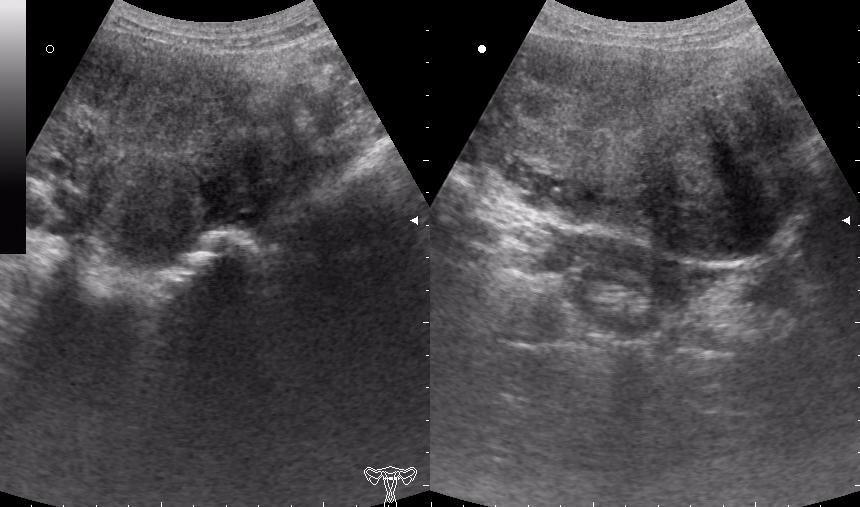

(девушке 23 года. фиброматоз матки)

по многочисленным письмам и заявкам телезрителей использована эксклюзивная опция - БОДИМАРКЕР!

ещё раз - это матка 23-летней девушки. то есть, ВСЁ это, то что Вы видите, да-да, на весь экран - это матка.

Диагноз - фиброматоз. направлена строго на север и налево. к соседям. (онкодиспансер)